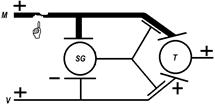

Каузалгию можно объяснить с позиций теории воротного контроля: При этом увеличивается поток импульсов к нейронам задних рогов спинного мозга — «ворота открываются». В спинном мозге или выше появляется генератор патологически усиленного возбуждения, образование которого обусловлено растормаживанием группы нейронов в связи с нарушением внешнего аппарата контроля, который локализован в поврежденной структуре (рис.).

Рис.. Объяснение каузалгии по теории воротного контроля.